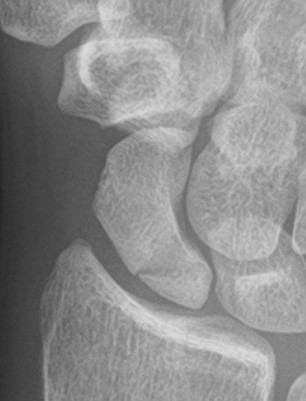

Scaphoid waist fracture 1 mm displaced

Scaphoid fracture with significant displacement

Scaphoid proximal pole fracture